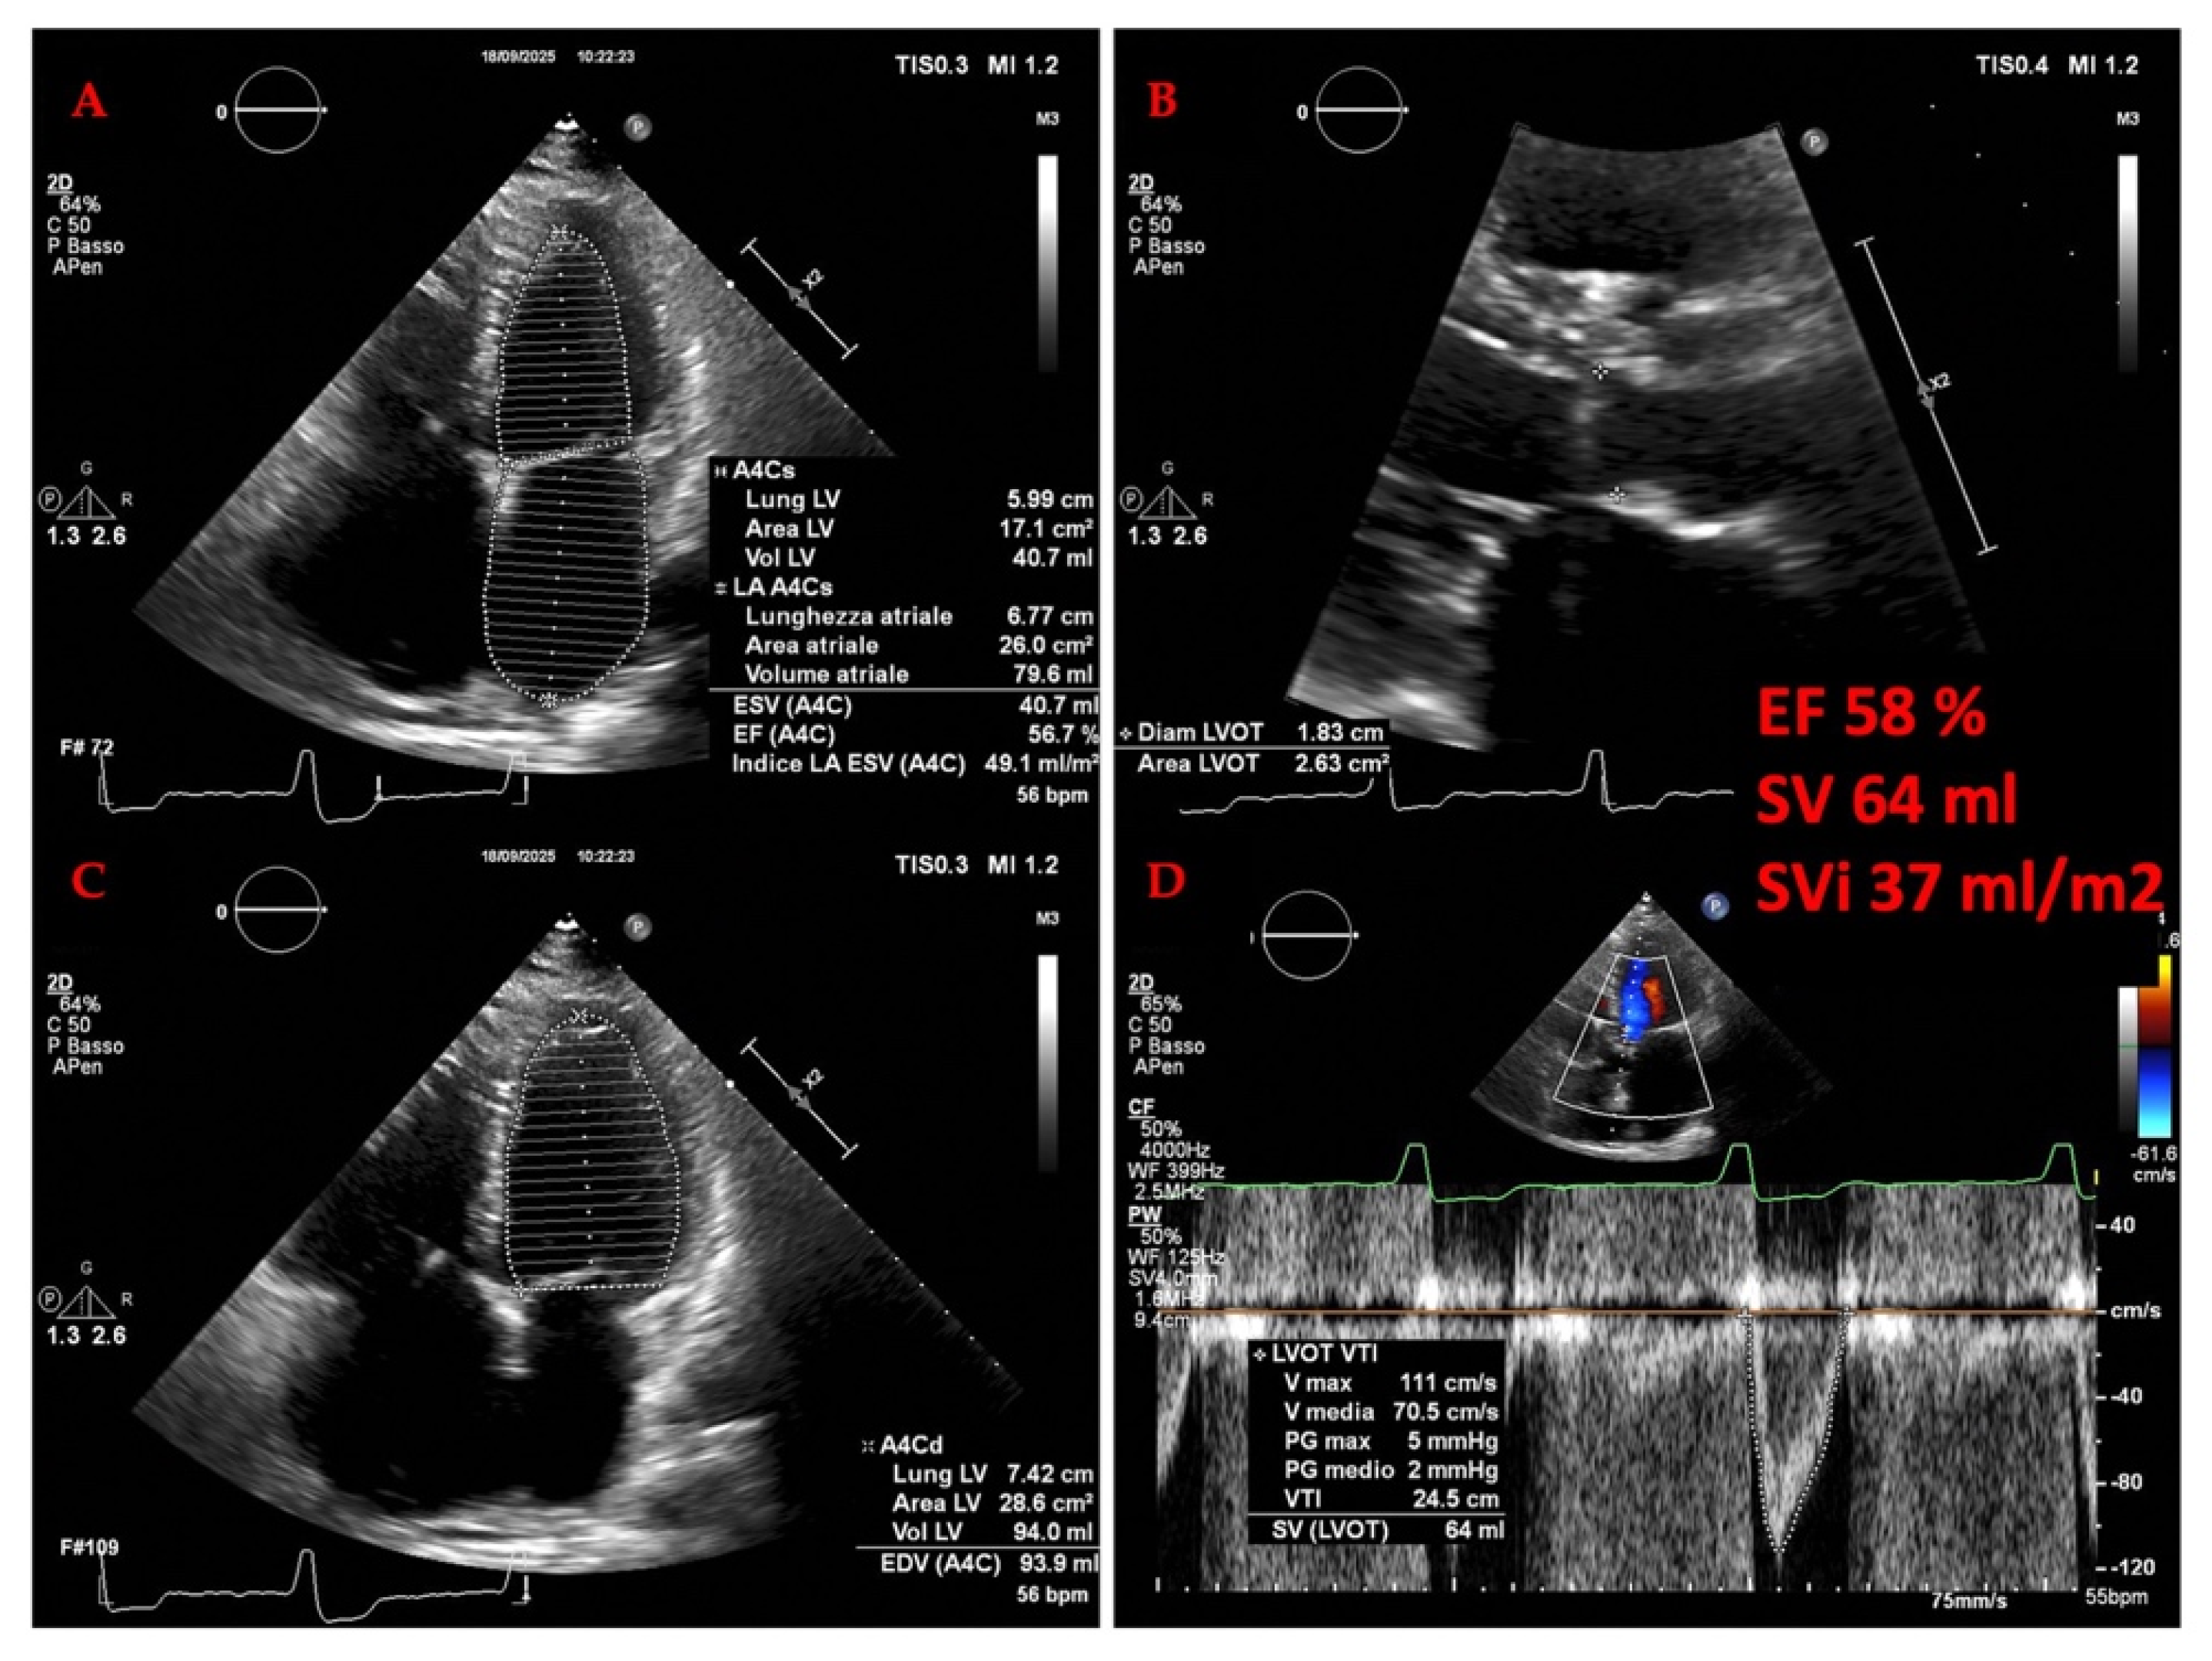

3.2.1. The Evolving Role of Echocardiography of Left Heart in Heart Failure

3.2.3. Echocardiography in Advanced Heart Failure